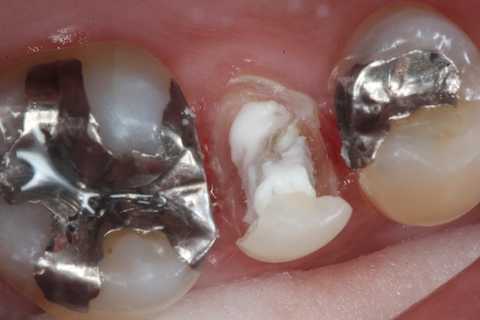

今日の充填治療55(遠心隣接面カリエス) 2023.12.21